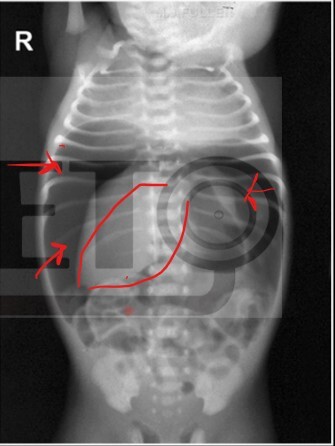

Estadio de Enterocolitis Necrosante en este paciente

llB: presencia de cisuras y gas en sistema portal ( higado )